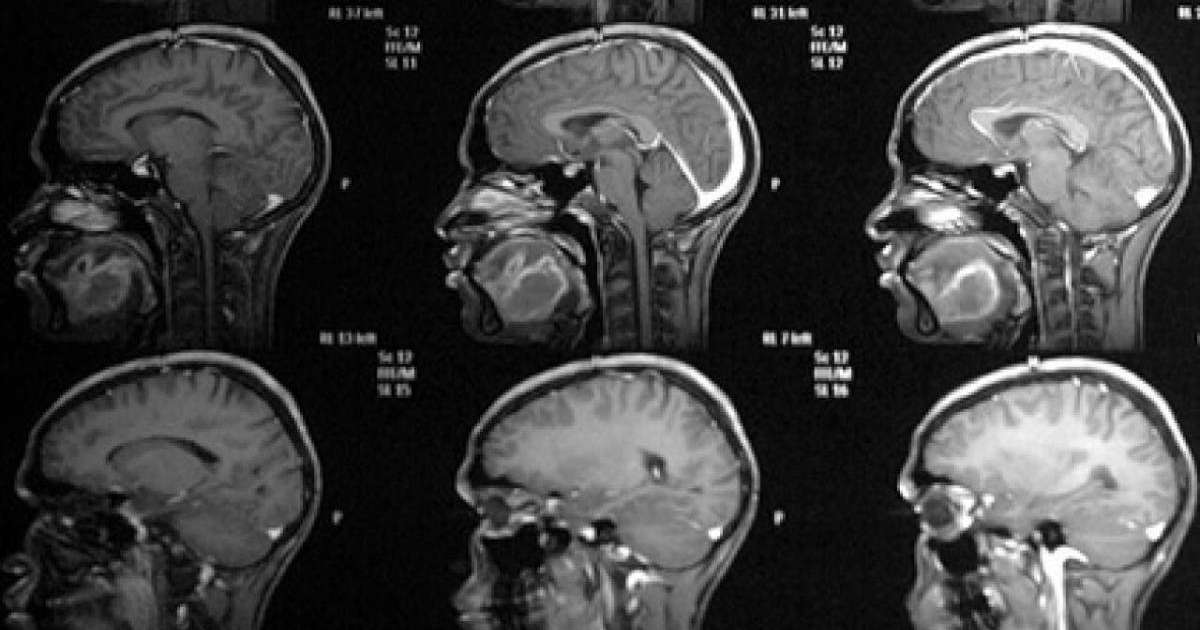

Дәрігер түсіндіргендей, ми қатерлі ісігі бірнеше типке ие болуы мүмкін: біріншілік - тікелей ми тіндерінде дамиды, сонымен қатар екінші реттік, бұл басқа органнан шыққан ісіктің метастазасы. Сонымен бірге ауруды ерте сатысында тану қиынға соғады. Негізі ол жалпы асимптоматикалық түрде дамиды.

"Ми ісігінің ең көп таралған симптомы - бас ауруы. Вестибулярлық функцияға жауапты органдар зақымданған кезде дұрыс сөйлей алмай қалады, сөйлеген кезінде сөз тіркестері мен әріптер түсіп қалуы мүмкін », - деп түсіндірді Мяснянкин Бесінші арнаға берген сұхбатында .

Мұндай белгілер пайда болған кезде пациент шұғыл түрде дәрігермен кеңесу керек екендігі атап өтіледі. Сондай-ақ, тез шаршағыштық, бас айналу, жүрек айну, естен тану, конвульсия, көру және есту қабілеттері бұзылған кезде назар аудару керек.